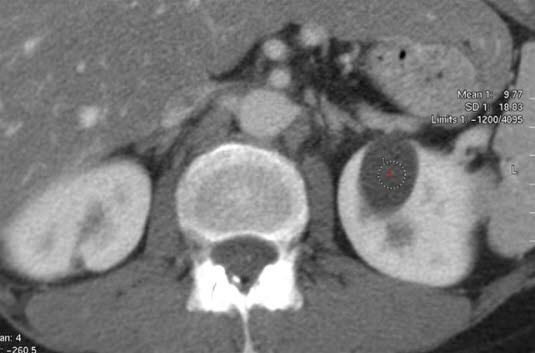

CT-bilde av nyrecysteSykdommen er arvelig, men selv om du har arvet de skadde arveanleggene (genene), så er ikke det ensbetydende med at du vil utvikle nyresvikt. Ved å studere arveanleggene har man funnet ut at det er to gener som kan være endret, og avhengig av hvilket gen som er skadet, skilles det mellom to hovedtyper (type 1-ADPKD - utgjør 85 prosent, type 2-ADPKD utgjør 15 prosent).

De avgjørende undersøkelsene er ultralyd eller CT hvor cystene kan påvises med sikkerhet. I tillegg tas blod- og urinprøver for å kartlegge nyre- og leverfunksjon. Ved mistanke om sykdom i blodårer kan annen bildediagnostikk være påkrevd.